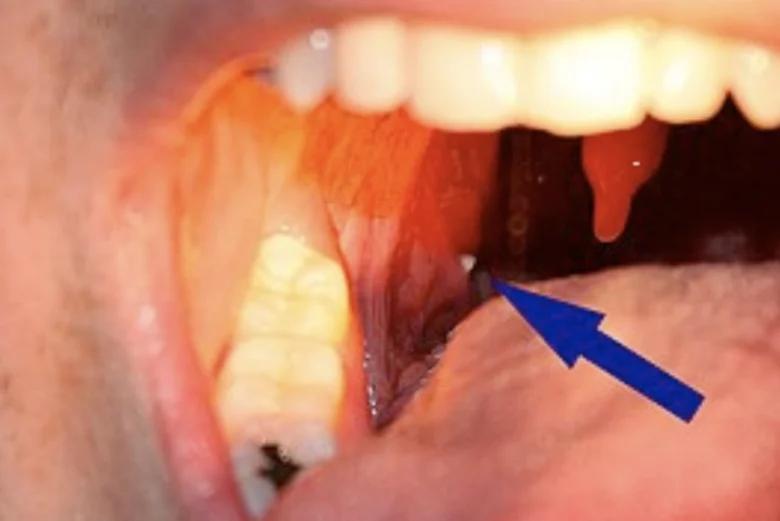

O que são, afinal, os cáseos amigdalianos? Os cáseos amigdalianos, também conhecidos como tonsilólitos, são pequenas formações brancas que se desenvolvem nas amígdalas. Essas pedras são causadas pelo acúmulo de resíduos orgânicos, restos alimentares e células descamadas da mucosa bucal. Quando esses materiais ficam presos nas criptas das amígdalas, combinam-se com o cálcio presente na …